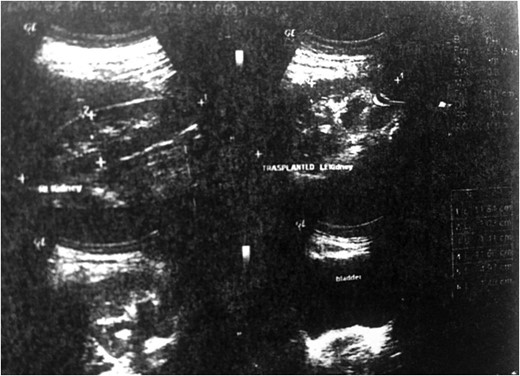

A ureteral catheter was inserted. A drainage tube was inserted to drain any possible bleeding from the operation site and then the surgical wound was closed. The patient was discharged in a good general condition after 3 days and the drainage tube removed. The ureteral stent was removed 4 weeks later by cystoscopy under local analgesia. An ultrasound imaging study of the genitourinary system 8 months into the patients follow up showed normal size, echo and cortical thickness in the operated kidney after renal autotransplantation.

Gray-scale ultrasonography of the patient's transplanted kidney 8 months after surgery.